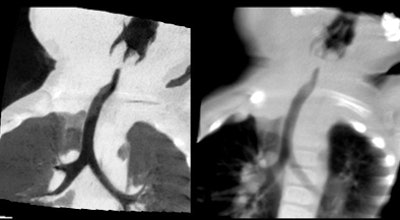

| Patient with stridor and giant cervical hemangioma was breathing continuously and not sedated during 320-detector-row CT, acquired in two rotations at 0.35 sec, 80 kV, 20 mA, and dose of 0.3 mSv. Below, additional rotation allows reconstruction of images at multiple time points, revealing air trapping that would have been missed at single-rotation scan. |